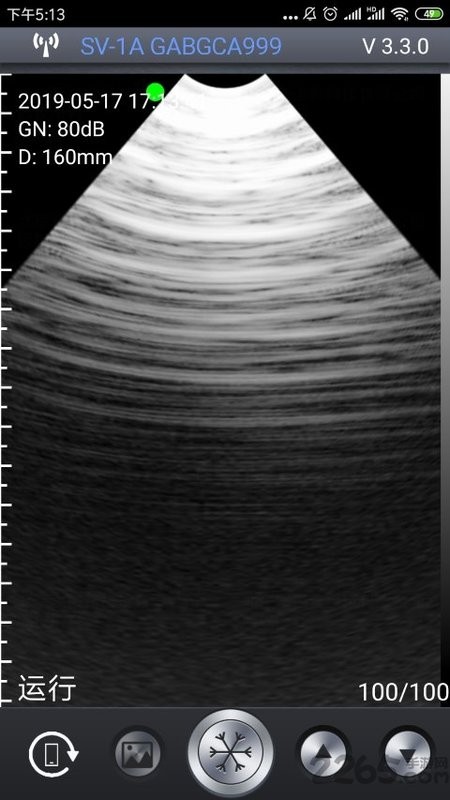

通过最强大的成像功能也是能让你查看到最全面的重要信息内容,任何图片信息都能够以最全面的方式为您介绍;

通过WiFi,以下多种型号的超声探头可以与该软件连接:HD-1,SV-1,SV-2,SS-1,SF-1,SU-2等。在这些不同配置的探头中,总有一款能够满足您的专业需求。